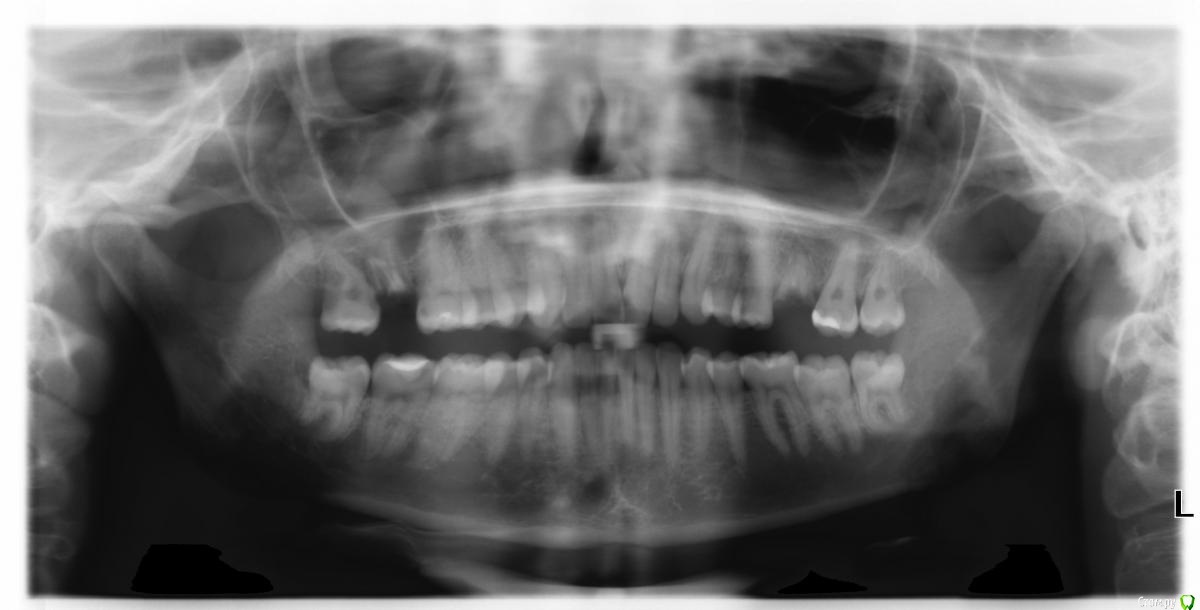

gum Опубликовано 29 апреля, 2015 Поделиться Опубликовано 29 апреля, 2015 (изменено) Обратилась пациентка с жалобами на тяжесть в подглазничный области справа, боли, иррадиирующие в область уха, висок, температуры с ее слов не было, 3 дня пьет обезболивающие препараты. Делаю снимок и ... Радикулярная киста с пенетрацией пазухи, при чём, я так понимаю нагноившаяся. Отправляю в члх они ее заворачивают обратно со словами идите удаляйте зуб туда, откуда вас прислали, возникнут осложнения приходите.Назначил пациентке антибиотик. Вопрос как ее вести после удаления зуба? Сталкиваюсь с данной ситуацией впервые. Изменено 29 апреля, 2015 пользователем gum Ссылка на комментарий